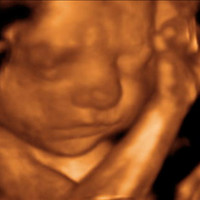

Stork Vision 3D 4D Center

Stork Vision prides itself on being the industry leader in Prenatal Ultrasound Imaging. To ensure the safety and quality of your ultrasound experience, all scans are performed by RDMS sonographers and are reviewed by an OB/GYN. Physicians and midwives nationwide prefer the high standards and consistent protocols of Stork Vision Centers for 2D, 3D and 4D limited diagnostic ultrasounds.

Interests: We offer 2D gender determination after 17 weeks and 3D 4D ultrasounds between 27-33 weeks.